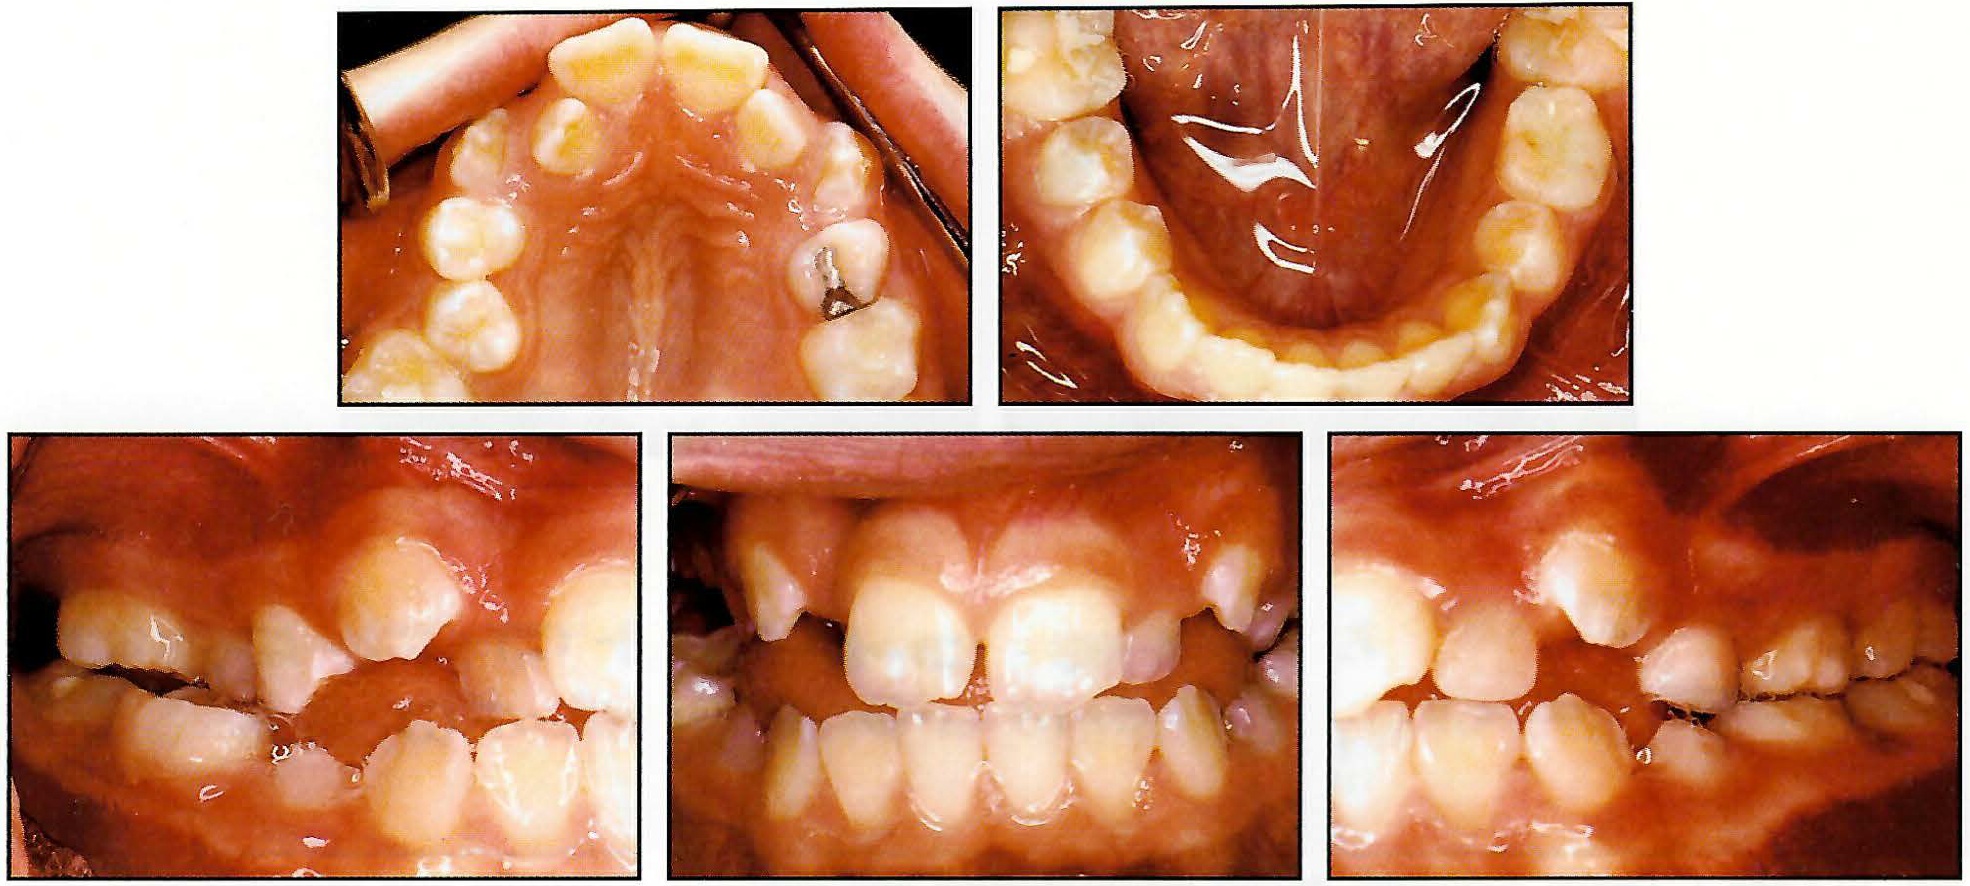

An 11-year-old postpubertal female presented with a slightly crowded dentition and a Class I occlusion (Fig. 12). The left posterior segment was in crossbite. The overjet and overbite were 2mm each.

Fig. 12 Case 2. 11-year-old female in late mixed dentition with unilateral posterior crossbite before treatment.